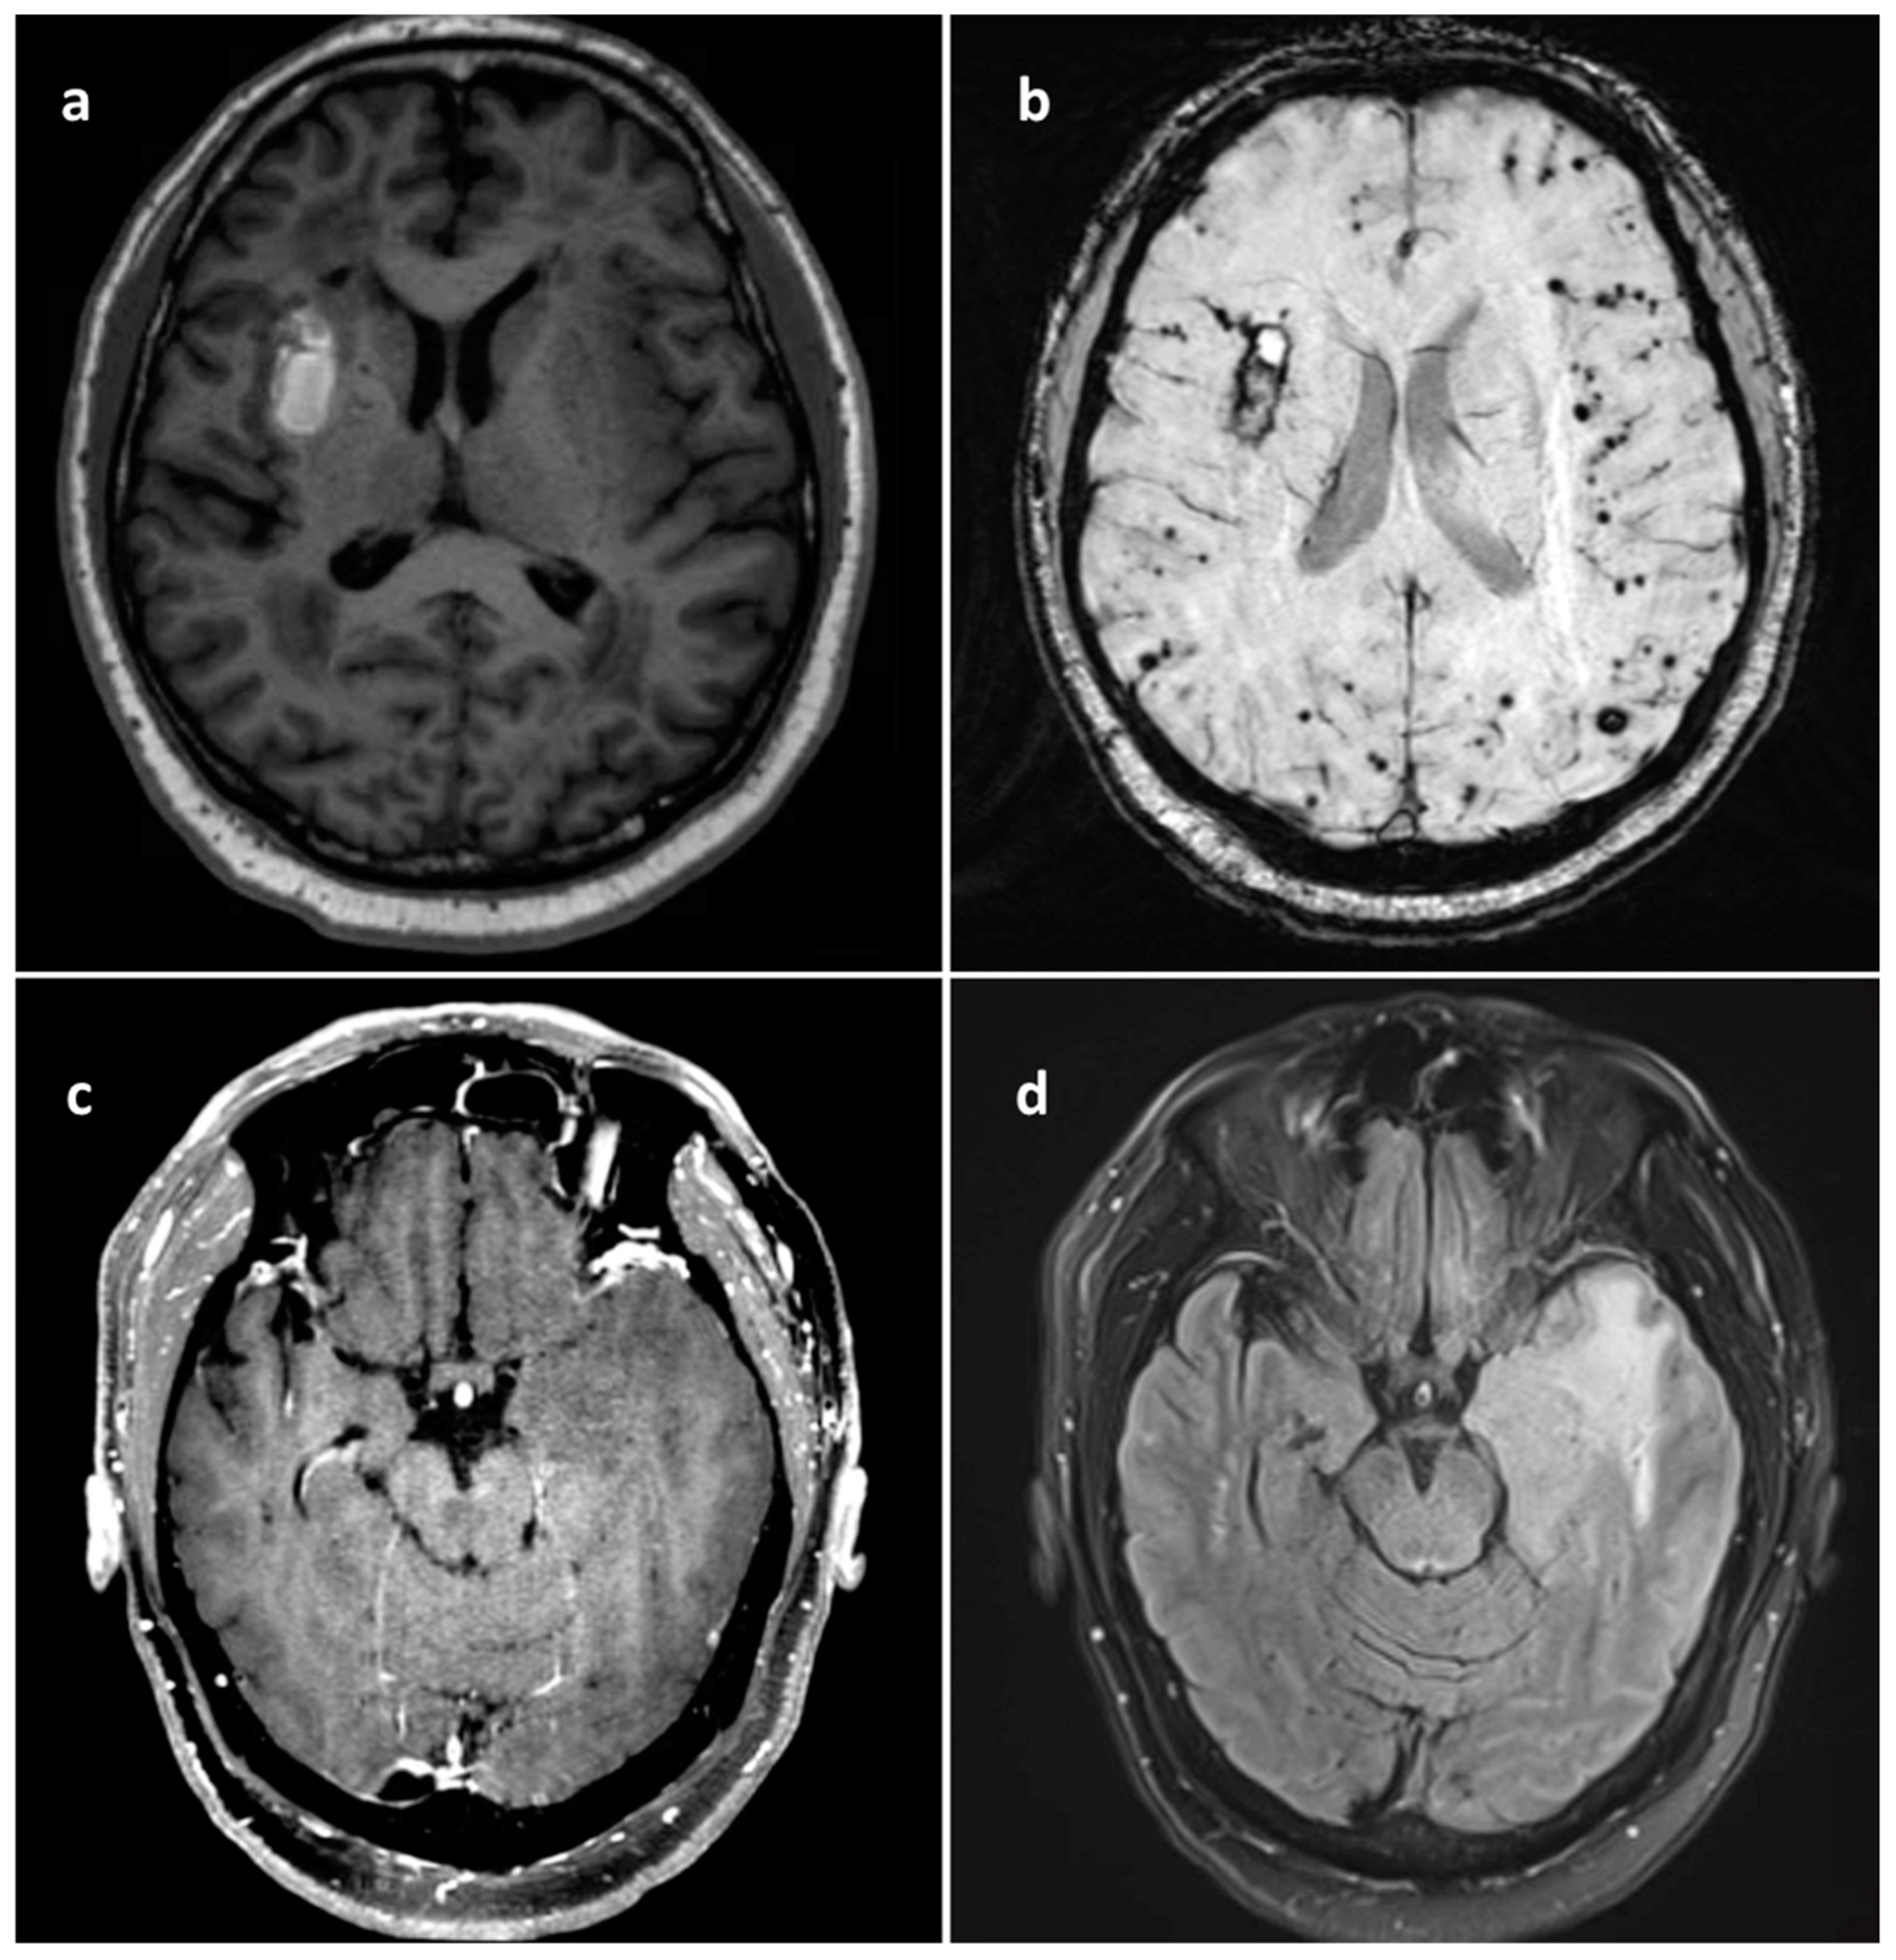

A 68-year-old male presented with gradually worsening symptoms of severe fatigue, inattentiveness, urinary incontinence, and memory impairments over seven months. Cognitive symptoms continued to escalate prompting an evaluation in the emergency department. Magnetic resonance imaging (MRI) of his brain revealed an area of evolving parenchymal hemorrhage in the right insula (Figure 1a), with innumerable foci of hemosiderin in cerebral and cerebellar hemispheres (Figure 1b) and a T2/FLAIR hyperintense mass in the left insular region without contrast enhancement (Figure 1c,d).

Figure 1. (a) Axial MRI T1 without contrast showing right basal ganglia hematoma. (b) Axial MRI SWI demonstrating numerous small microvascular hemorrhages predominantly within subcortical white matter of bilateral cerebral hemispheres along with the more peripherally focused right basal ganglia subacute hematoma, overall concerning for cerebral amyloid angiopathy. (c) Axial MRI T1 with gadolinium contrast without evidence of any left temporal insular tumor enhancement. (d) Axial MRI T2 FLAIR revealing infiltrating left temporal insular tumor.